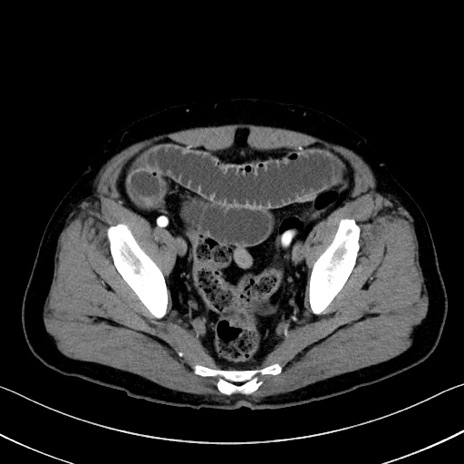

冠状断像

【症例】70歳代 男性

【主訴】腹部膨満、嘔吐

【現病歴】昨日より腹部膨満感出現。本日増悪し、仙痛出現。嘔吐あり、受診。

【既往歴】糖尿病、胆摘後

【身体所見】BP 149/80mmHg、HR 74/min、BT 35.9℃、腹部:膨満、軟、圧痛なし。腸雑音減弱あり。上腹部正中切開瘢痕あり。

【データ】WBC 13500、CRP 1.72